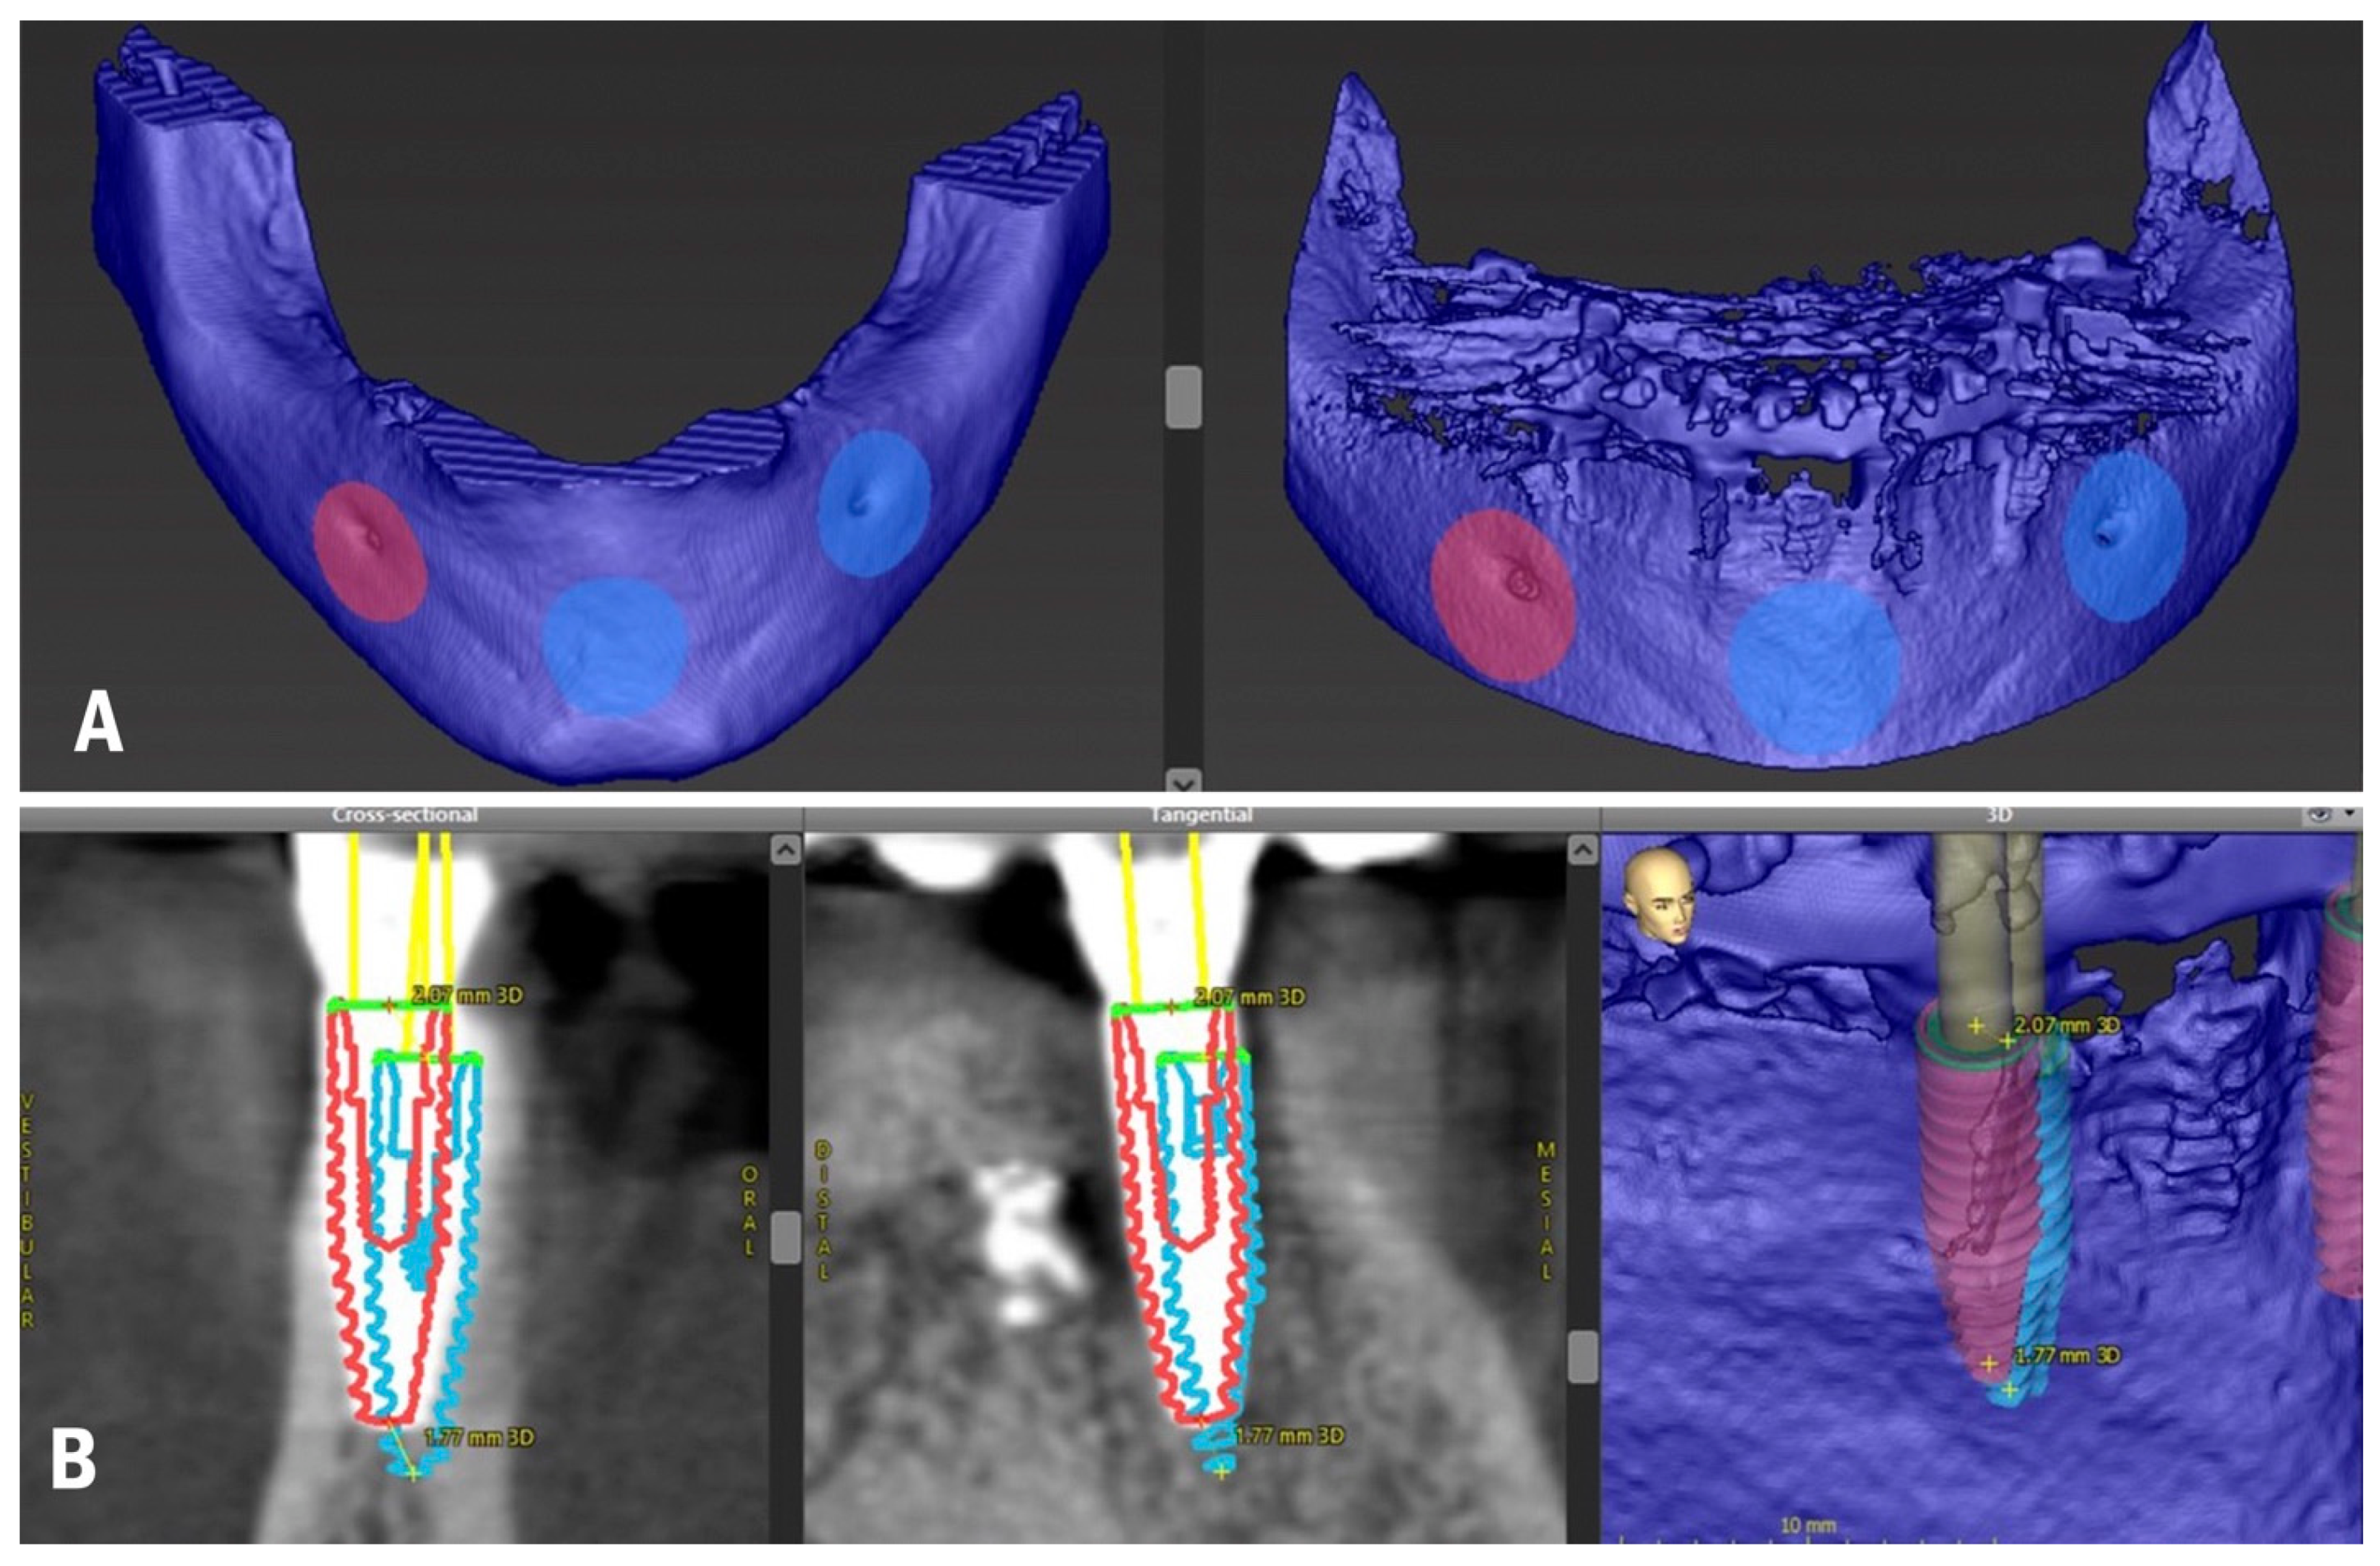

2. Materials and Methods

2.1. Planning and Surgery

3.1. In Vivo Treatment Evaluation

3.2. In Vitro Treatment Evaluation